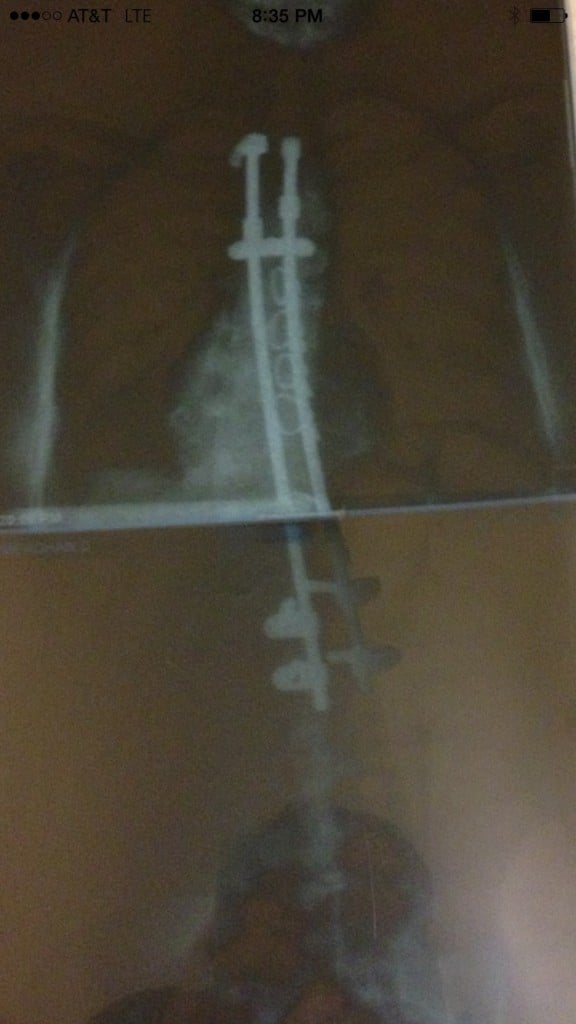

On May 14, 2007, Dr. Rawlins and his team proved to be the most competent and compassionate professionals I have ever met. Over the course of several hours, they performed my operation while also reassuring my family that everything was alright. During my nine day stay at the hospital, Dr. Rawlins personally came to check on me several times. The nursing staff was there for me during all hours of the day and night. They even brought me a birthday cake and sang to me on my 21st birthday. Yes, I know, most people do not spend their 21st birthday in the hospital recovering from a major operation. At least they made it enjoyable! Dr. Rawlins and everyone at Hospital for Special Surgery made it possible for me to be a healthy and happy person. Since my surgery, I am able to participate in all of the sports and activities I was able to beforehand and so much more! I am back to snowboarding, running, and even participated in the City to Shore bike ride last year. I love participating in charity runs and can only hope that one day I can partake in one that supports HSS or a scoliosis group!

I strive to stay as healthy and active as possible. To me, it is the least I can do after being given a second chance at a healthy body. Looking at your own x-rays of 70 degree curves and being told your lung capacity will soon be affected makes scoliosis scary. HSS provided me an opportunity to exchange those x-rays for straighter ones and for that, I am eternally grateful. Although I am just one of Dr. Rawlin's thousands of patients, he will always be my number one doctor. I am thankful to him for his medical expertise, support to my family, and calming personality. He is a remarkable man who does so much for many people. He has donated a great deal of his time and resources to his home country of Ghana, so that the children their can also live happy and healthy lives. If we could all strive to adopt his giving personality, this world would be a better place! Thank you Dr. Rawlins and HSS!